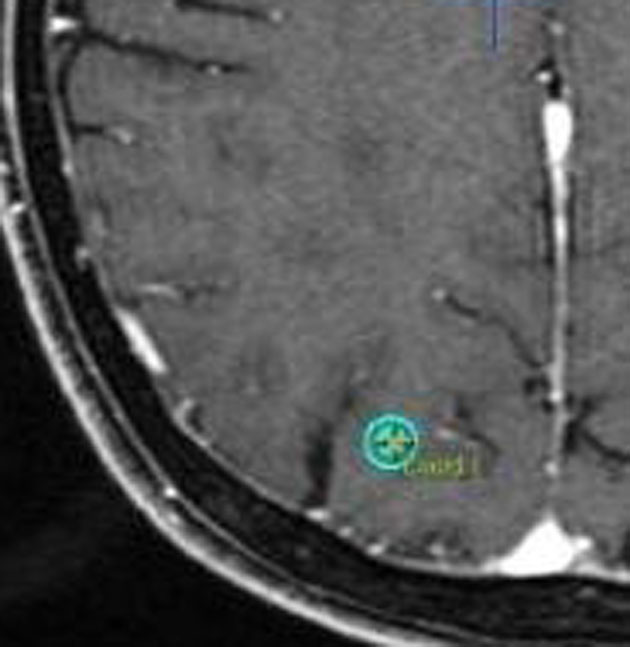

放射線外科 SRS の治療計画です。左側のとても小さな脳転移にたいして,中心線量25グレイ,辺縁線量20グレイの計画です。黄色の線より外にはほとんど放射線が入らない治療です。でも周辺脳が全く被曝しないわけではありません。